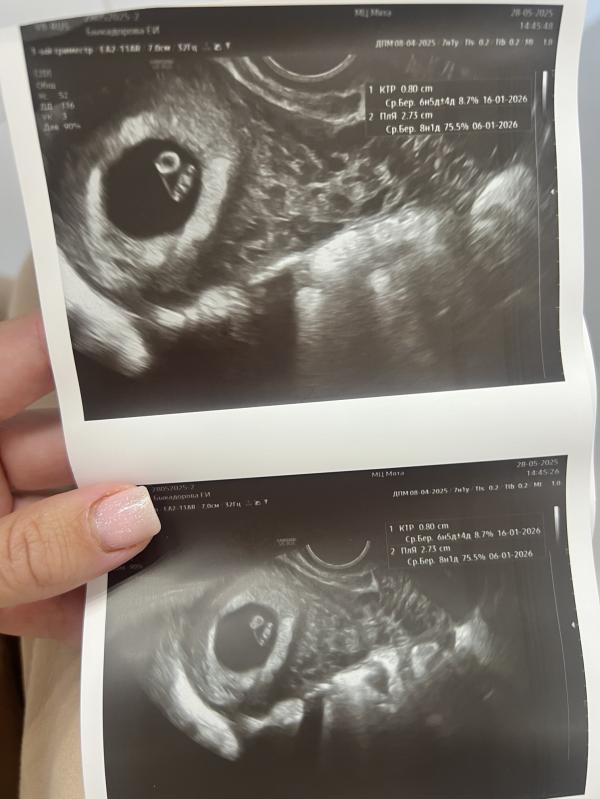

Растет наша креветочка🤍😍

По узи все замечательно. Сердечко бьется быстро 152 уд.мин.